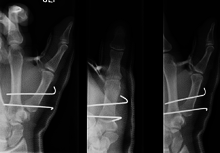

Bennett's fracture repair

Though these fractures commonly appear quite subtle or even inconsequential on radiographs, they can result in severe long-term dysfunction of the hand if left untreated. In his original description of this type of fracture in 1882, Bennett stressed the need for early diagnosis and treatment in order to prevent loss of function of the thumb CMC joint, which is critical to the overall function of the hand.[3]

Regardless of which approach is employed (nonsurgical, CRPP, or ORIF), immobilization in a cast or thumb spica splint is required for four to six weeks.